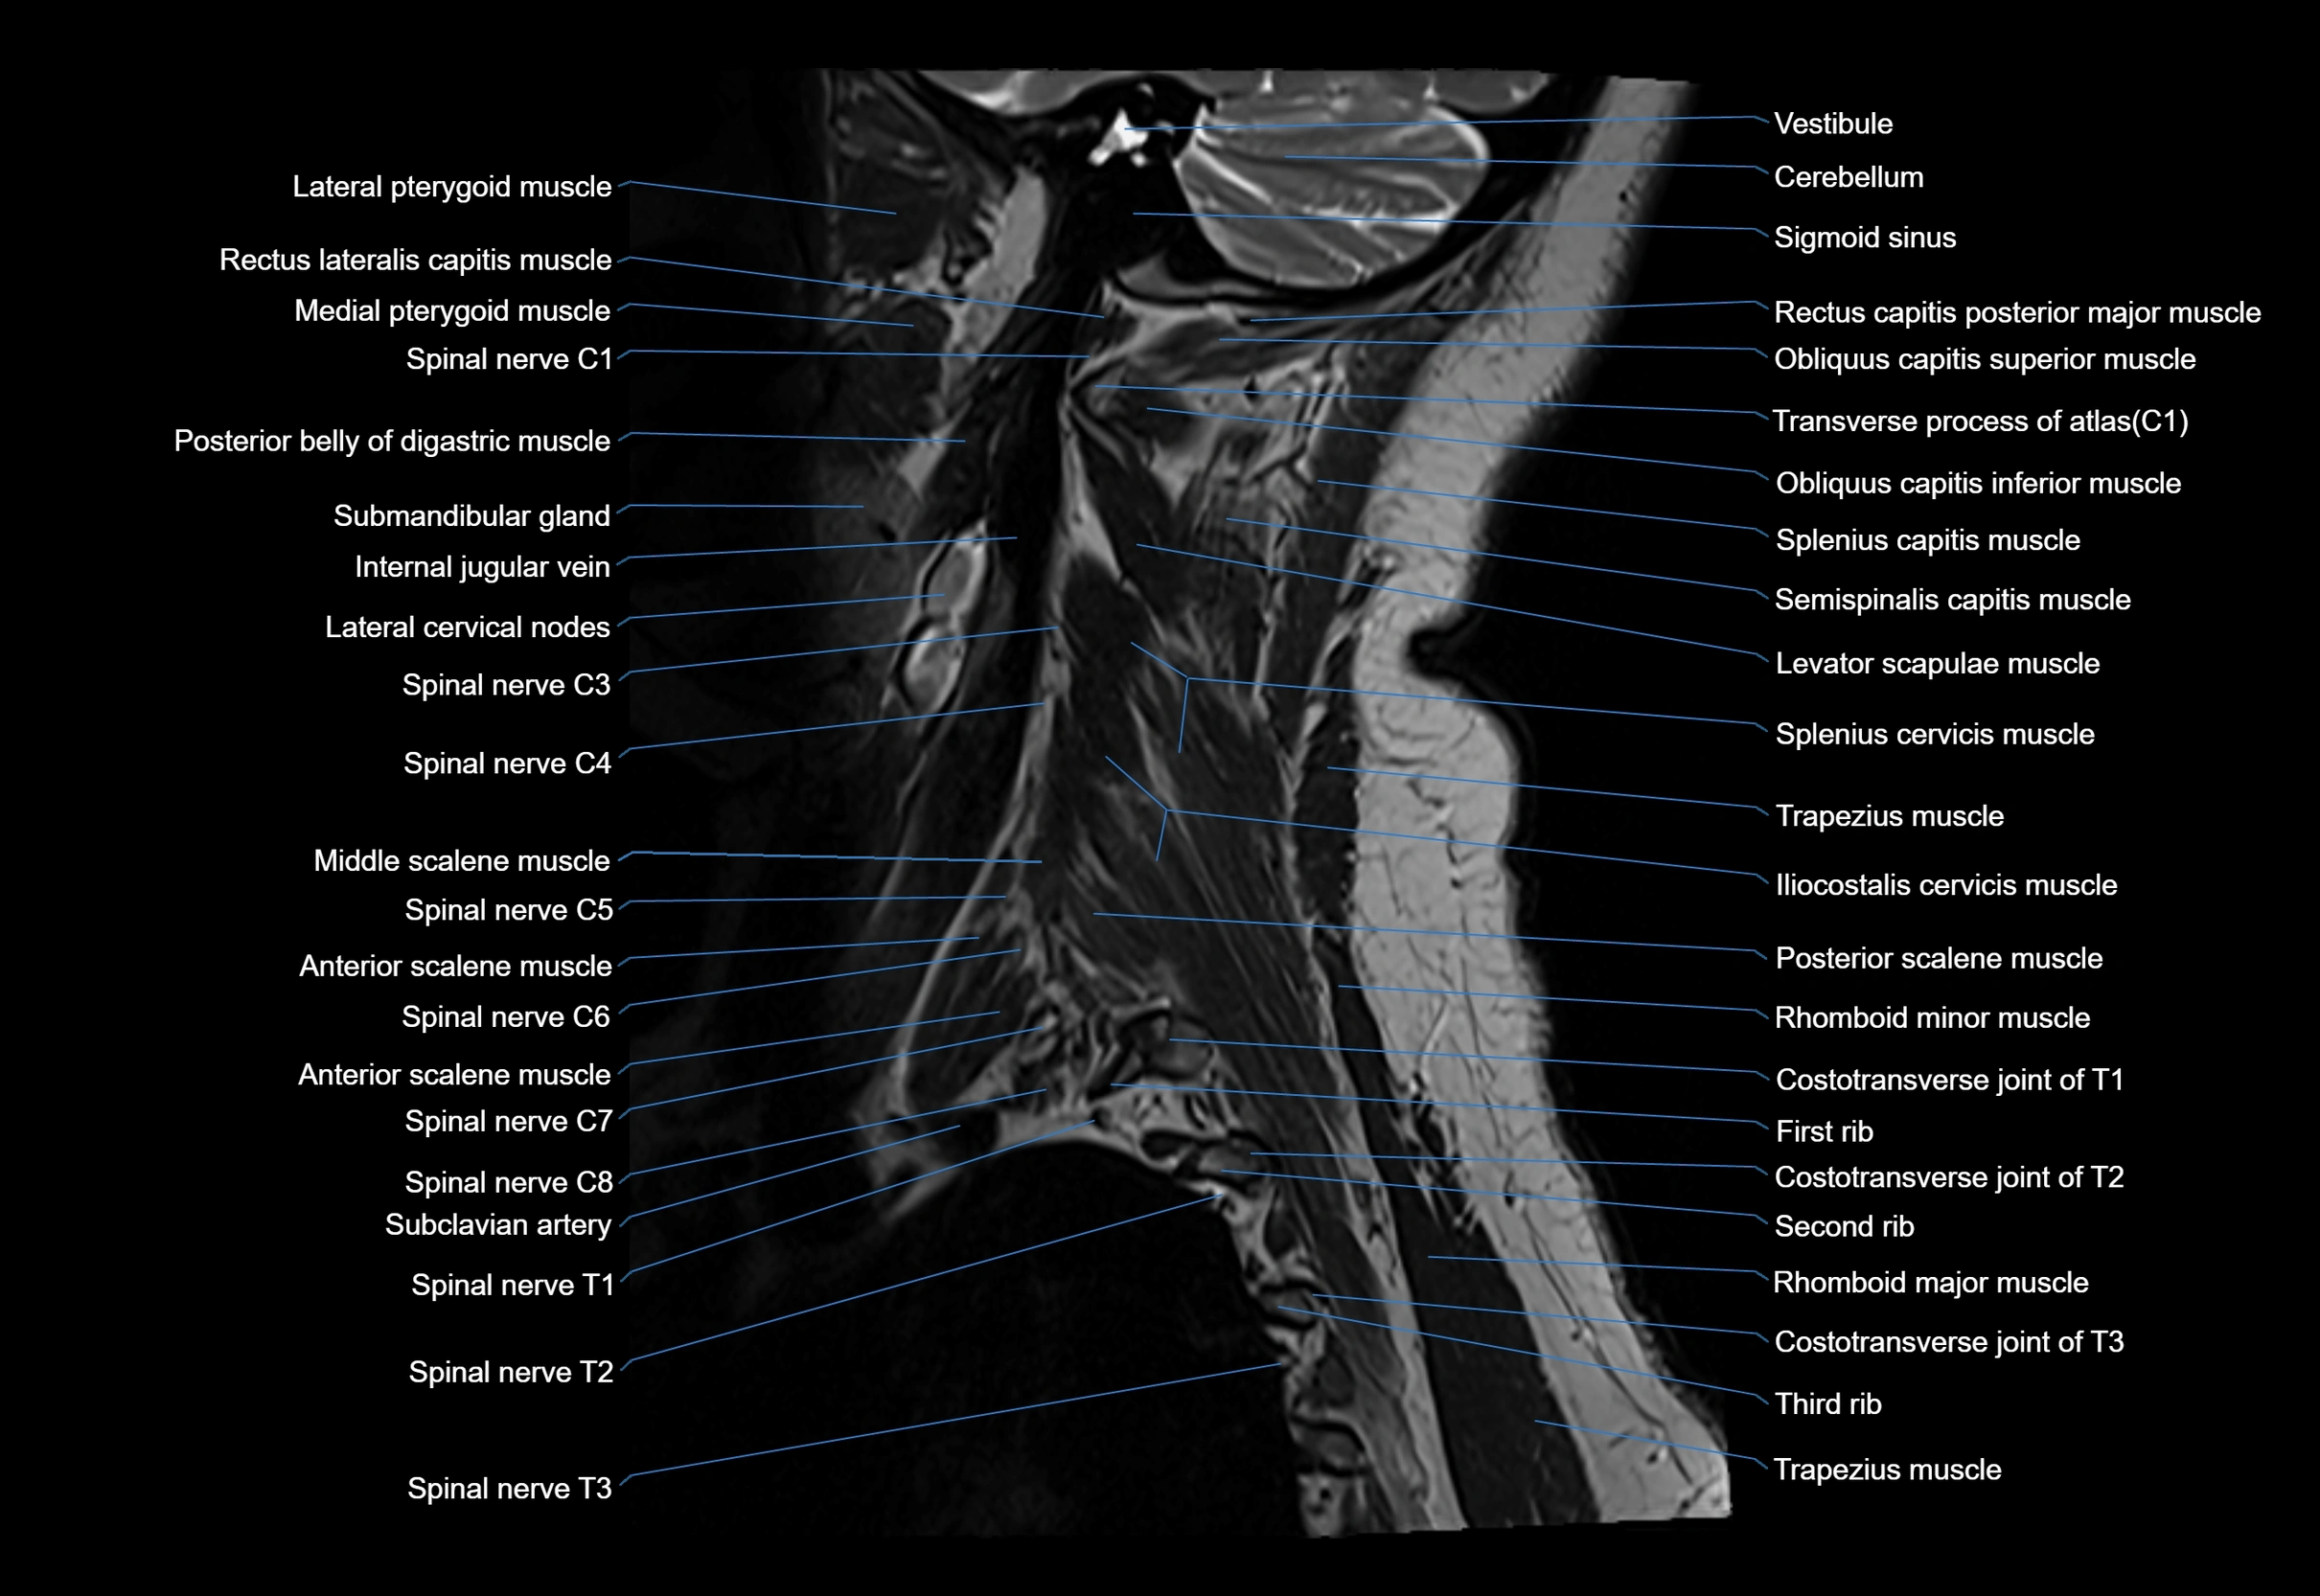

MRI appearance

T1-weighted images:

• Annular epiphysis: Low signal cortical rim at the vertebral margin

• Adjacent marrow: Intermediate-to-high signal in the vertebral body

• Disc interface: Clear delineation between bone and annulus

T2-weighted images:

• Annular epiphysis: Low signal intensity line

• Endplate cartilage (in younger patients): Intermediate signal

• Intervertebral disc: High signal nucleus pulposus

STIR:

• Annular epiphysis: Low signal cortical rim

• Adjacent marrow: Suppressed fat signal with preserved bony outline

• Utility: Highlights marrow and endplate interface in developing spine

MRI image

image